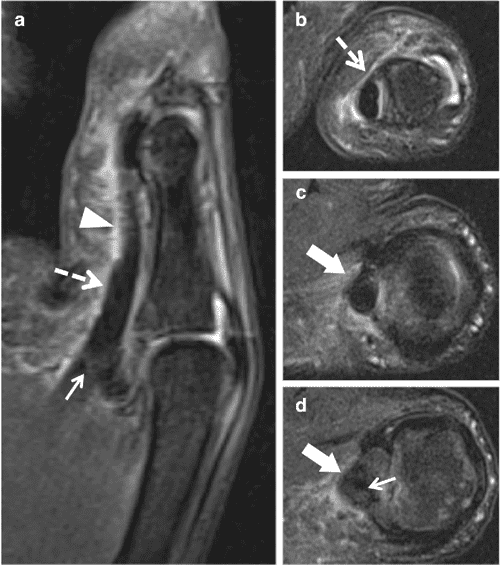

The annular pulley system of the thumb (arrows) of a 48year old female